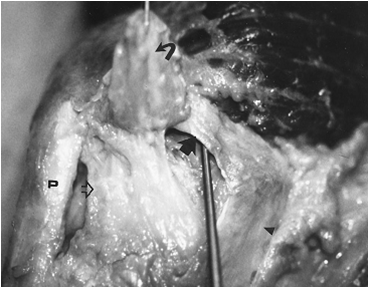

In cadaveric studies, one can see that if the MPFL is cut, the restraint to lateral kneecap dislocation becomes much less.